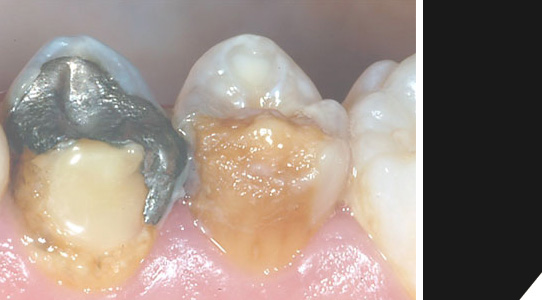

Wahl- o. Kassenleistung | Keramikfüllung

Die "Batterie im Mund". Amalgam ist ein äußerst umstrittenes Thema. Immer noch gehört eine Füllung mit diesem giftigen Material zur Kassenleistung. Aufgrund des unschönen Erscheinungsbildes und des allergieauslösenden Befundes bei manchen Patienten, entscheiden sich viele nach einigen Jahren sowieso dafür, Ihre Füllungen beispielsweise durch hochwertige Keramik ersetzen zu lassen.